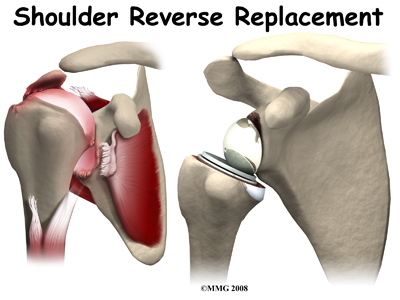

The answer to this dilemma was to rethink the mechanics of the shoulder joint and to design an artificial shoulder that worked differently than the real shoulder joint. The solution was to reverse the socket and the ball, placing the ball portion of the shoulder where the socket use to be and the socket where the ball or humeral head use to be.

This new design led to a much more stable shoulder joint that could function without a rotator cuff. The artificial joint itself provided more stability by creating a deeper socket that prevented the ball from sliding up and down as the shoulder was raised. The large deltoid muscle that covers the shoulder could be used to more effectively lift the arm, providing better function of the shoulder. The final result is a shoulder that functions better, is less painful and can last for years without loosening.

The reverse shoulder prosthesis (artificial joint) is made up of two parts. The humeral component replaces the humeral head, or the ball of the joint. The glenoid component replaces the socket of the shoulder, which is actually part of the scapula.

The reverse shoulder prosthesis (artificial joint) is made up of two parts. The humeral component replaces the humeral head, or the ball of the joint. The glenoid component replaces the socket of the shoulder, which is actually part of the scapula.

In the traditional artificial shoulder prosthesis, the glenoid prosthesis is a shallow socket made of plastic and the humeral component is a metal stem attached to a metal ball that nearly matches the anatomy of the normal shoulder. In the reverse shoulder replacement, the ball and the socket are reversed such that the ball sticks out of the shoulder itself.

The humeral component is a combination of a metal stem that fits into the marrow cavity of the upper humerus and, on top of the metal stem, a plastic socket. This plastic socket fits onto the humeral component to create a ball and socket type bearing. The glenoid component is usually made of two parts: a metal tray and a metal ball. The metal tray (base plate) attaches directly to the bone. This base plate is inserted into a small peg hole drilled into the bone and is secured with special screws through the base plate into the bone. Attached to that metal tray, there is a metal ball that will fit into the plastic socket attached to the humeral component. The plastic is very tough and very slick, much like the articular cartilage it is replacing. This plastic is so tough that you could actually ice skate on a sheet of this plastic without causing it much damage.